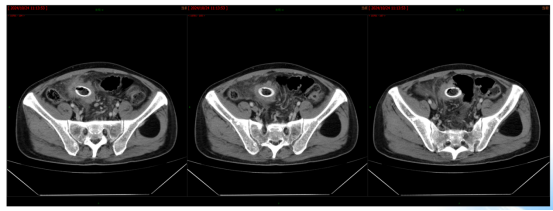

影像学检查:2024年7月30日,院外腹部CT显示乙状结肠管壁增厚,考虑肿瘤性病变(cT3N2,图1),2024年8月5日,肝脏MRI显示肝脏多发转移灶(侵犯门静脉右支、肝右静脉,图2)。2024年8月2日胸部CT显示双肺结节待排(图3)。

图1. 腹部CT